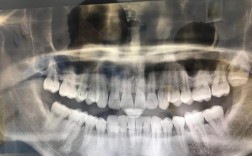

- 在决定是否进行正畸前,必须进行全面的牙周检查,包括牙周探诊(测量牙周袋深度)、牙龈出血指数、牙槽骨状况(通过X光片评估)、牙齿松动度等。